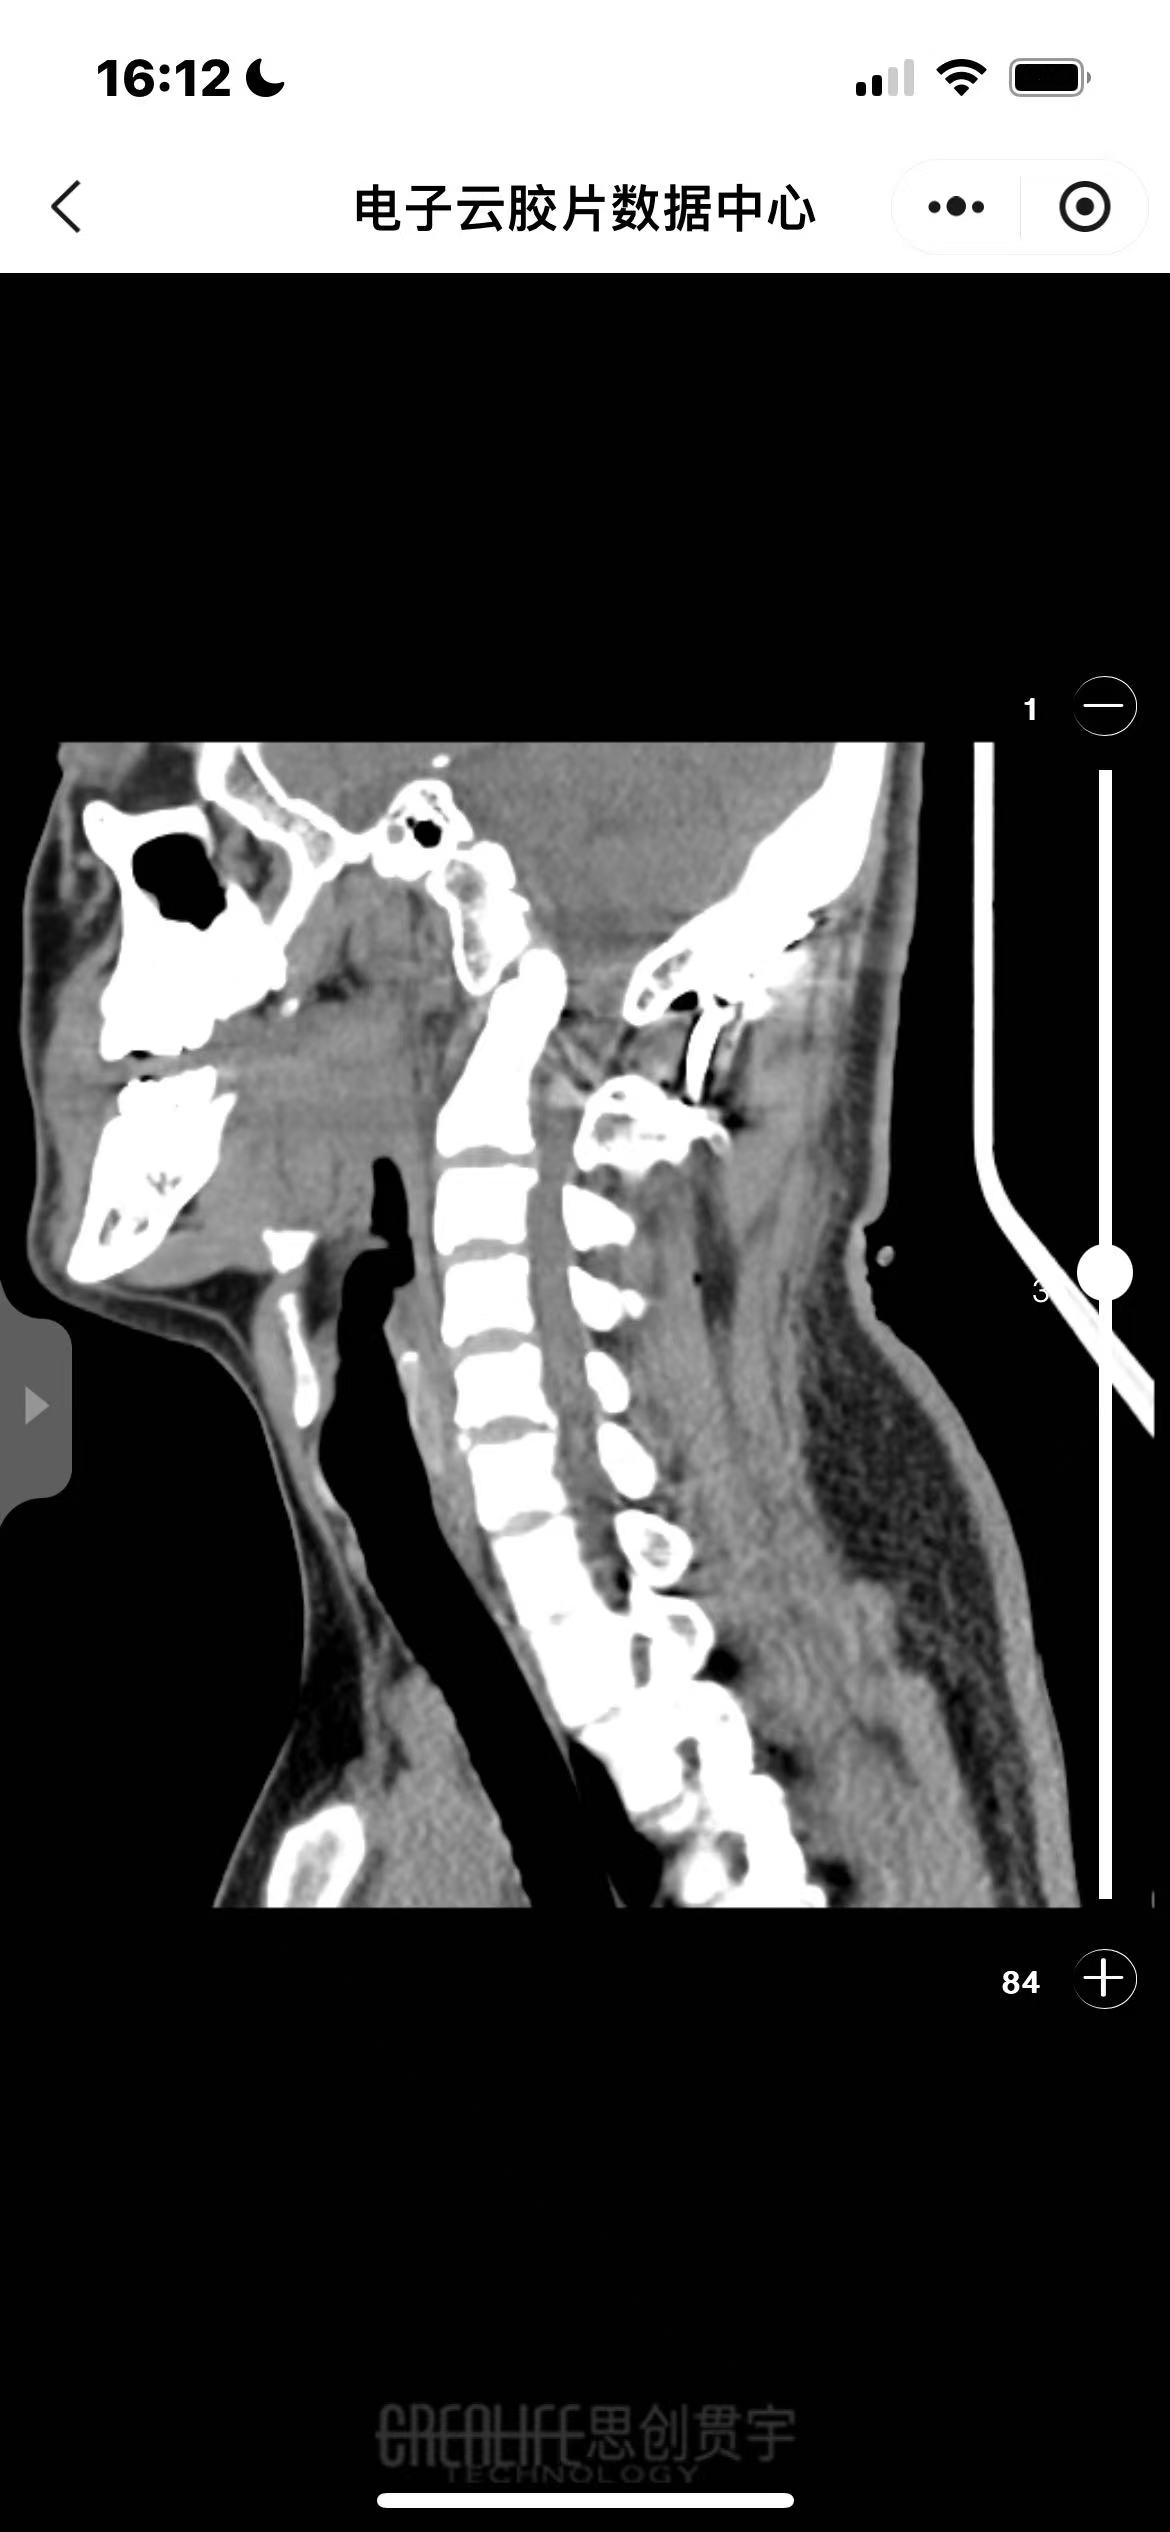

• 诊断:寰枢椎脱位、颅底凹陷

• 影像: